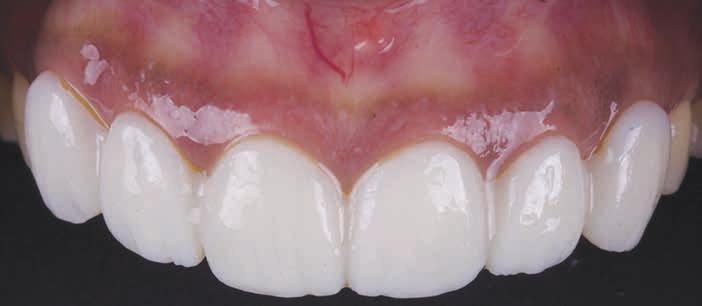

For situations in which APE is present concomitant with existing prostheses or compromised tooth conditions such as wear, caries, large restorations, or trauma, prosthetic rehabilitation is necessary to achieve satisfactory results. When restorative treatment is indicated, the presurgical plan begins with determining the proposed incisal

Figure 3. Chu proportion gauge (T-bar).

edge position on the basis of tooth display in repose and during smiling.35 Once established, the mean length to width ratio is calculated, and the level of the future gingival margin is determined accordingly. Such measurements are transferred to stone casts and diagnostic waxing is performed to predict the final crown dimensions.

The restorative dentist can then prepare teeth and place artificial crown margins at the level of the proposed gingival margin before the actual crown lengthening surgery. The prepared finish lines will serve as a surgical guide from which the periodontist will apically position the alveolar bone crest by 3 mm.

place provisional crowns before crown lengthening owing to lack of adequate retentive and resistance form.37 Laboratory-fabricated surgical guides can also be beneficial in cases that do not require restorative treatment (Figure 4).